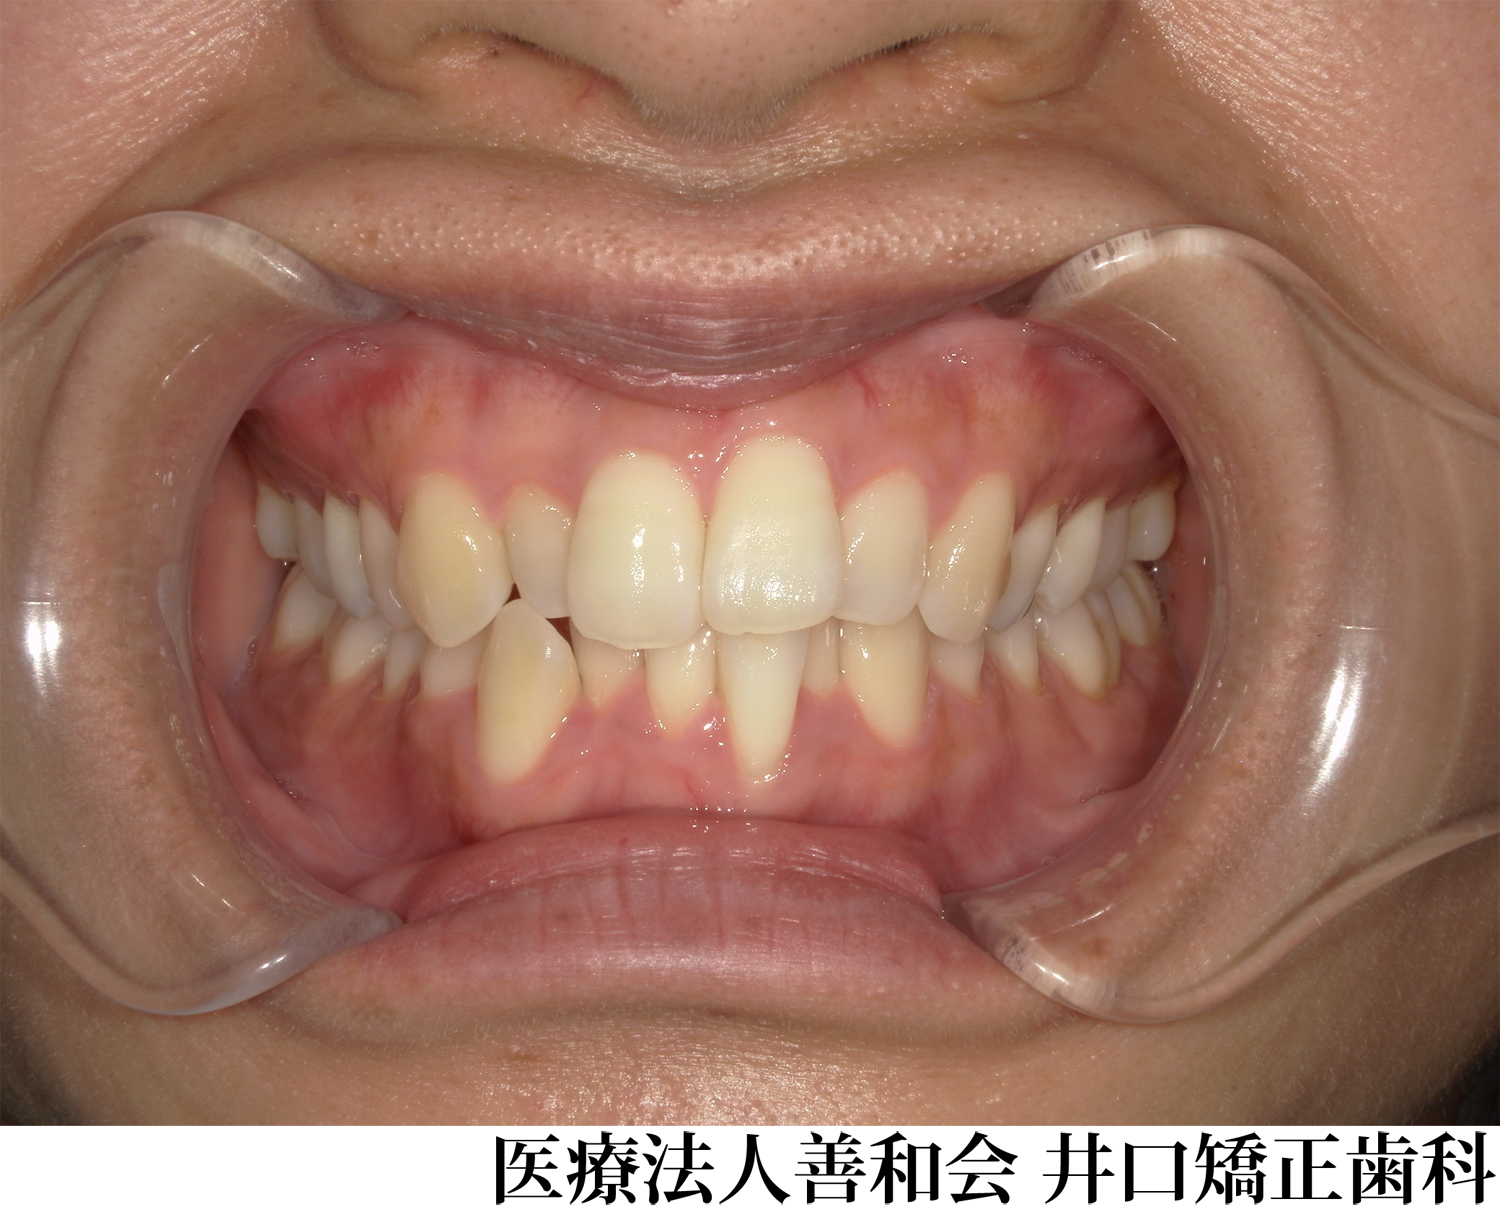

¡Ú¾ÉÎã2¡Û¥Þ¥¦¥¹¥Ô¡¼¥¹·¿¥«¥¹¥¿¥à¥á¥¤¥É¶ºÀµÁõÃ֤Ǽ£ÎŤò¹Ô¤Ã¤¿À®¿Í¶ºÀµ¤Î¾ÉÎã(¥¤¥ó¥Ó¥¶¥é¥¤¥ó»ÈÍÑ)

- ¼£ÎÅÁ°

- ¼£ÎŸå

- ¥Þ¥¦¥¹¥Ô¡¼¥¹·¿¥«¥¹¥¿¥à¥á¥¤¥É¶ºÀµÁõÃ֤Ǽ£ÎŤò¹Ô¤Ã¤¿À®¿Í¶ºÀµ¤Î¾ÉÎã(¥¤¥ó¥Ó¥¶¥é¥¤¥ó»ÈÍÑ)

¼£ÎÅÆâÍÆ

´µ¼ÔÍͤξɾõ

±ü»õ¤Î°ÌÃÖ´Ø·¸¤Ï´ð½à¤È¤Ê¤ë¤È¤³¤í¤«¤é¼õ¤±¸ýÊý¸þ¤Ë¥º¥ì¤Æ¤ª¤ê¡¢Á°»õ¤Î³ú¤ß¹ç¤ï¤»¤Ï·ÚÅÙ¤ÎÈ¿ÂÐÒû¹ç¤È¤Ê¤Ã¤Æ¤¤¤¿¡£

¾å¤ÎÁ°»õ¤ËÁÑÀ¸(»õ¤Ê¤é¤Ó¤Î¥¬¥¿¥¬¥¿)¤òǧ¤á¡¢¤Þ¤¿¿âľŪ¤Ë¤â³«Òû¤È¤Ê¤Ã¤Æ¤¤¤¿¡£ -

¼£ÎÅË¡

¥Þ¥¦¥¹¥Ô¡¼¥¹·¿¥«¥¹¥¿¥à¥á¥¤¥É¶ºÀµÁõÃÖ¤ò»ÈÍѤ·¡¢ÈóÈ´»õ¤ÇÇÛÎó¤ò¹Ô¤¤¤Þ¤·¤¿¡£

¼£ÎÅ·ë²Ì

±±»õ´Ø·¸¤Î¥º¥ì¡¢Á°»õ¤ÎÈ¿ÂÐÒû¹ç¡¢³«Òû¤Ï²þÁ±¤·¤Þ¤·¤¿¡£